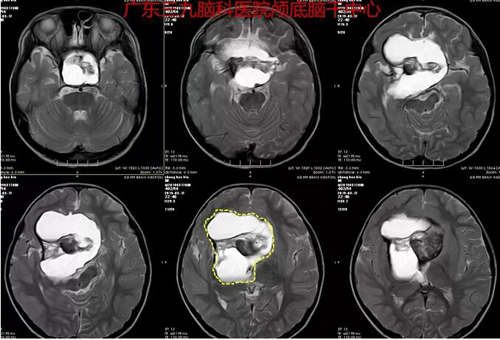

图2:术前MR示鞍上-鞍上区(突破鞍隔至蝶窦)示团片异常信号,T2W1序列呈高信号为主,其内示团片状低信号影,考虑颅咽管瘤可能性大。

图3:术前术后MR对比,肿瘤全切除。